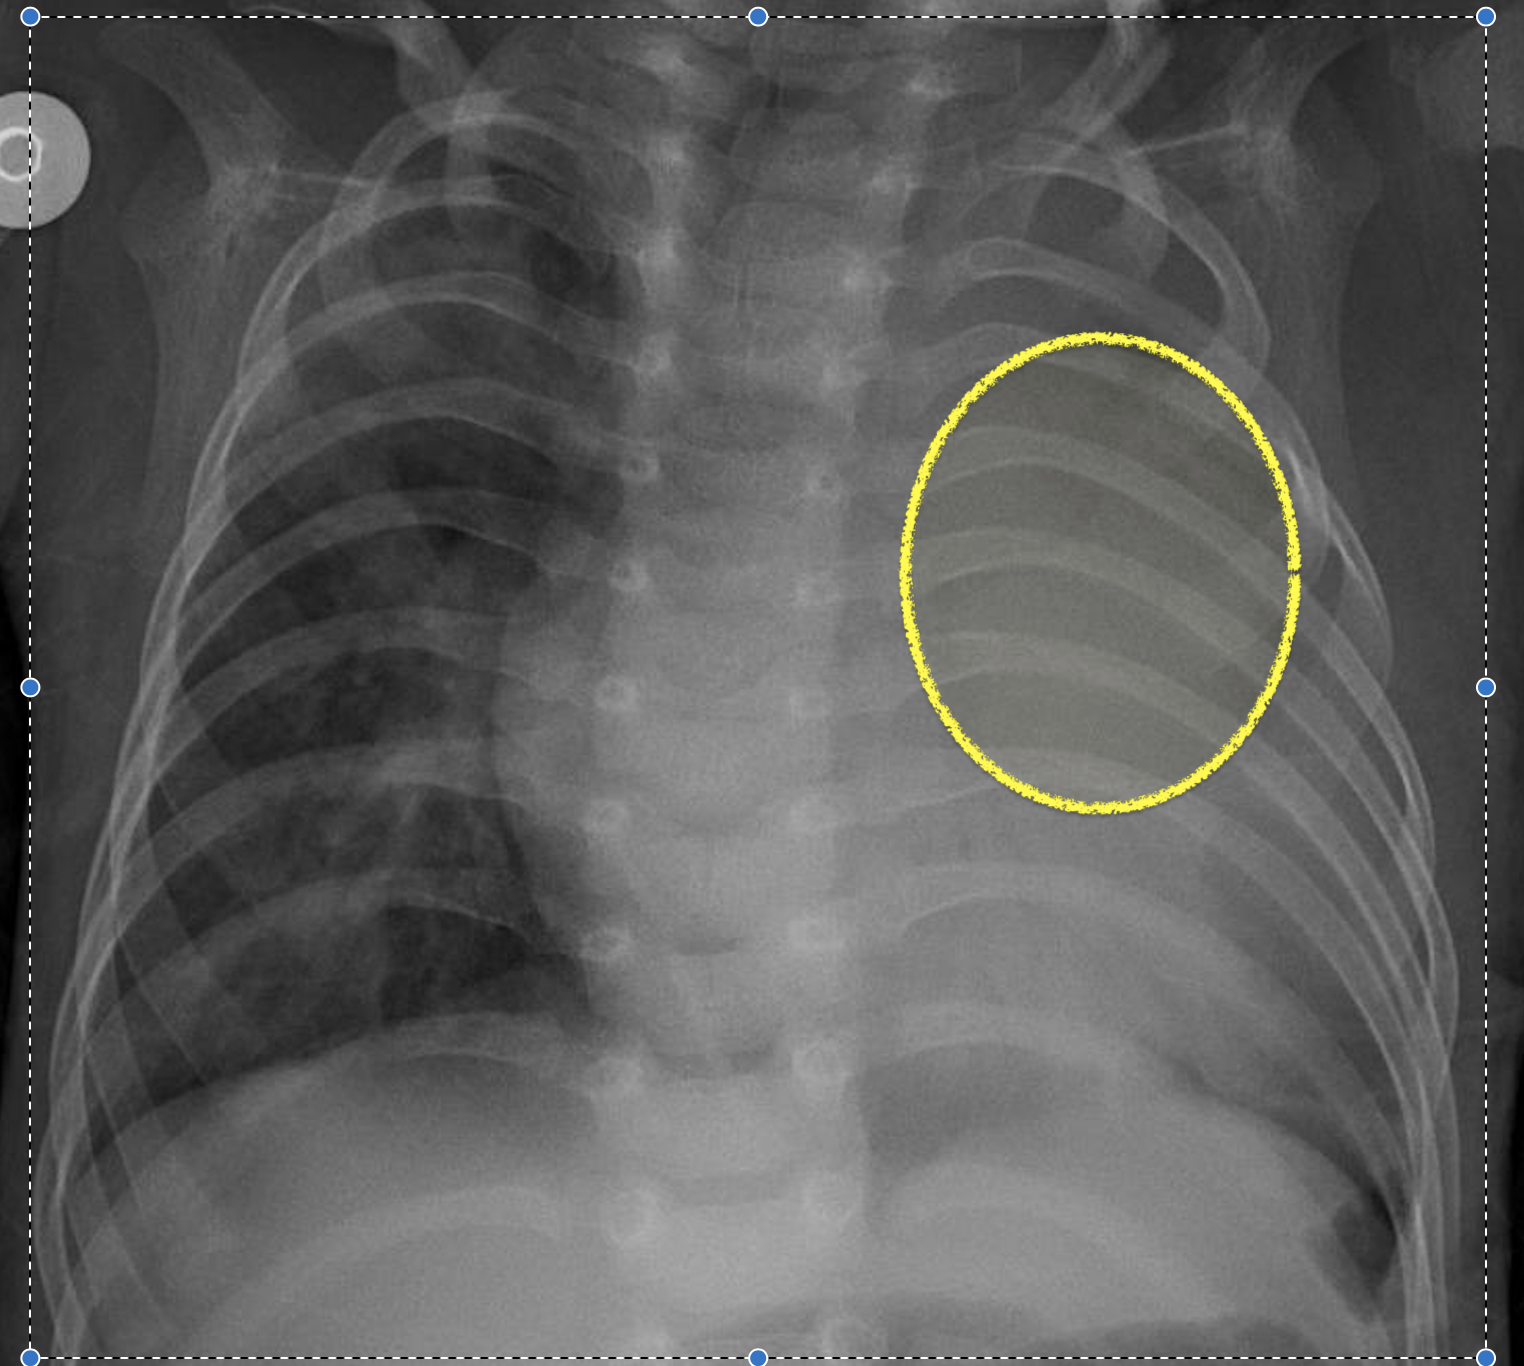

We employ a large-scale of chest X-ray dataset COVIDx [20] to validate the proposed model. It is comprised of 18,543 chest radiography images across 13,725 cases. Example chest X-ray images belonging to normal, pneumonia, and COVID-19 classes from COVIDx dataset are shown in Figure 2. When we examine these examples, we can differentiate these images in terms of features shown within areas marked by the blue circle since we can observe some lighter areas indicating COVID-19 infected regions in the blue circle.